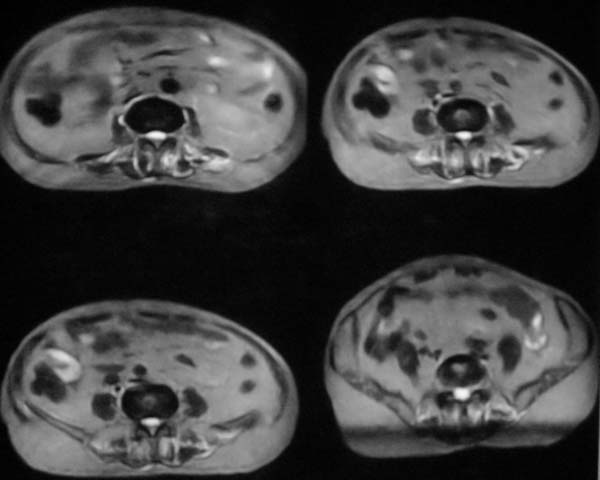

病史特点:

1.中年男性

2.腰疼,双下肢麻木1月。

3.ct 可右肾上腺占位,腰1椎体及附件可见骨质破坏及软组织肿块。

4.mri:腰1椎体及附件t1wi低信号,t2wi高信号。

考虑右侧肾上腺癌骨转移.或右肾上腺及骨均为转移瘤。